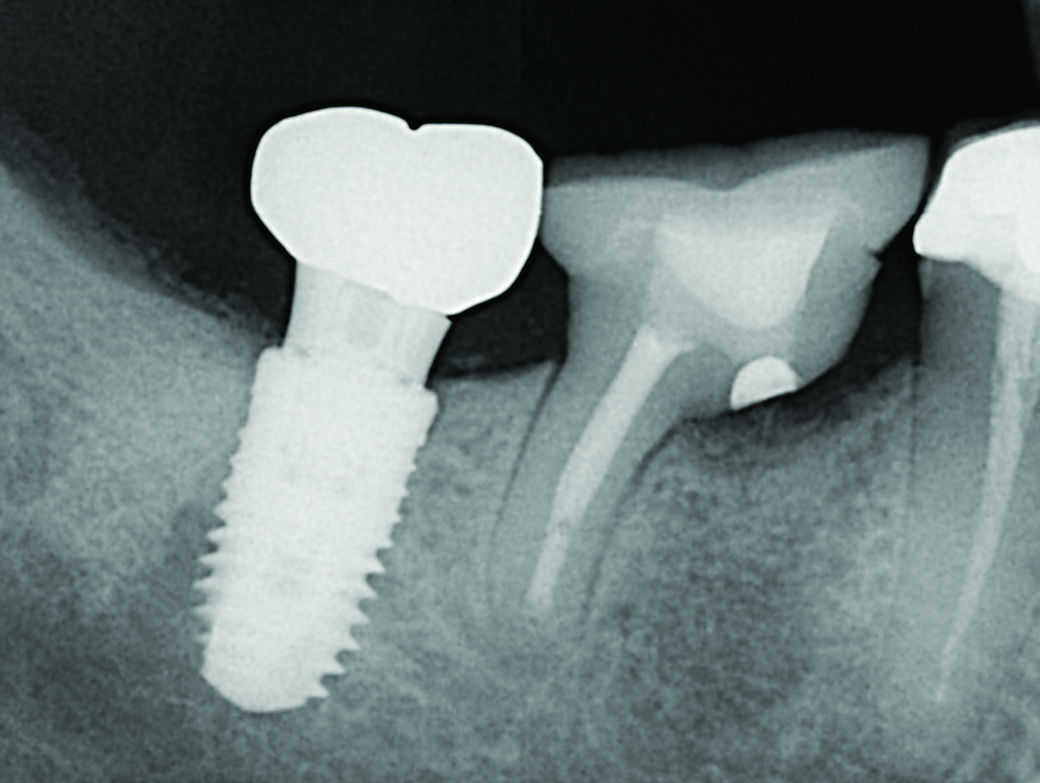

Such compromised conditions include vertically fractured roots, perforated roots, periodontally compromised roots due to furcation or root proximity issues, communicating endodontic-periodontal defects compounded by short root lengths, unresponsive furcation defects, significant untreatable external resorptive defects, and so on (Figure 1 through Figure 4). When conditions such as these affect single-rooted teeth, extraction is often the only way to eliminate the resultant pathology. With multirooted teeth, however, an additional option exists: definitively removing the cause of the pathology while simultaneously retaining the tooth in a functional state, which has published favorable survivability rates of upwards of 80% to 90%.1-3 If performed appropriately by taking into account the factors described in this article, this functional state can be maintainable for the long term, with a median survival time of 6 to 20 years.3-6

Fig 1. Examples of multirooted teeth showing periradicular periodontitis and loss of periradicular bone support isolated to one root (indicated by red arrows). Fig 1: Tooth No. 3 distobuccal root with circumferential bone loss from the crestal bone height to the apex with stable mesiobuccal and palatal roots. Fig 2: Tooth No. 30 with a prior apical surgery showing bone loss surrounding a fractured mesial root. Fig 3: Tooth No. 19 with lateral and apical bone loss regions affecting a fractured mesial root. Fig 4: 3D CBCT imaging of tooth No. 3 depicting an apicomarginal bone loss defect affecting the mesiobuccal root with stable fused distobuccal and palatal roots.

Fig 1 through Fig 4. Examples of multirooted teeth showing periradicular periodontitis and loss of periradicular bone support isolated to one root (indicated by red arrows). Fig 1: Tooth No. 3 distobuccal root with circumferential bone loss from the crestal bone height to the apex with stable mesiobuccal and palatal roots. Fig 2: Tooth No. 30 with a prior apical surgery showing bone loss surrounding a fractured mesial root. Fig 3: Tooth No. 19 with lateral and apical bone loss regions affecting a fractured mesial root. Fig 4: 3D CBCT imaging of tooth No. 3 depicting an apicomarginal bone loss defect affecting the mesiobuccal root with stable fused distobuccal and palatal roots.